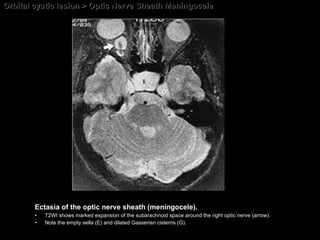

Optic Nerve Sheath Meningocele Saccular dilatation of the meninges surrounding the orbital portion of the optic nerve. Occur primarily or secondarily in association with other orbital processes, such as meningioma, optic nerve pilocytic astrocytoma, and hemangioma.  Present with changes in visual acuity or visual field.   (optic nerve sheath cyst, arachnoid cyst, perioptic hygroma, and dural ectasia)

Optic Nerve Sheath Meningocele The CT and MR imaging; Prominent focal or segmental enlargement of the dural arachnoid sheath around the optic nerve  May be associated with an empty sella. May be associated with enlarged subarachnoid cisterns (optic nerve sheath cyst, arachnoid cyst, perioptic hygroma, and dural ectasia)

Orbital cystic lesion > Optic Nerve Sheath Meningocele Ectasia of the optic nerve sheath (meningocele).  T2WI shows marked expansion of the subarachnoid space around the right optic nerve (arrow).  Note the empty sella (E) and dilated Gasserian cisterns (G).